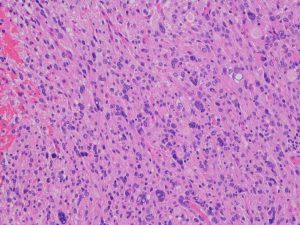

星細胞 astrocytesが強い多型性 pleomorphism を示すのでこの名があります

グリオーマの場合は核多型性というのは悪性ということと同義になることが多いのですが,この腫瘍の場合はそうではありません,著しい核の多型性のために,悪性腫瘍とくに退形成性星細胞腫や膠芽腫と誤診しないことが重要です,脂肪滴を含むlipitized cells(黄色の矢印)が混在 することもあります(xanthomatous change)

reticulin fiberに囲まれeosinophilic granular bodiesを含む特徴的な組織像を示します。時に神経細胞由来の腫瘍細胞を含みます (neuronal differentiation)

多単核細胞の核異型から多核の巨細胞まで見られますが,分裂像はなくMIB-1 indexは低いのが特徴です

lipidized cells (胞体に空胞が見られるastrocyte), pleomorphic / polynuclear astrocytes, perivascular lymphocyte infiltration, macrophageの集簇などがみられます。著明なmacrophageの浸潤があります。lipidized cellsが見られない場合にはanaplastic astrocytomaとの鑑別がHE染色のみでは難しいと考えて下さい。MIB-1は1%でした。